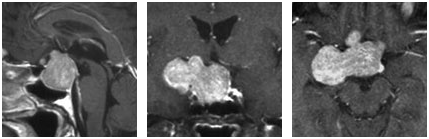

56岁患者出现了明显的视力下降和视野受限的问题,同时伴有垂体功能不足。影像检查发现一个大型无功能性垂体瘤。

磁共振成像(MRI)检查揭示了一个位于右侧、紧靠垂体区域的大型垂体腺瘤,并且该肿瘤在注射对比剂后呈现吸收现象。

术中操作:肿瘤不仅向上延伸至大脑的中线区域,而且还扩展到了右侧的颞叶,对周围的脑组织和神经结构造成了潜在的威胁。在经过细致的评估和审慎的考虑之后,施罗德教授决定采取分两阶段进行的手术策略。